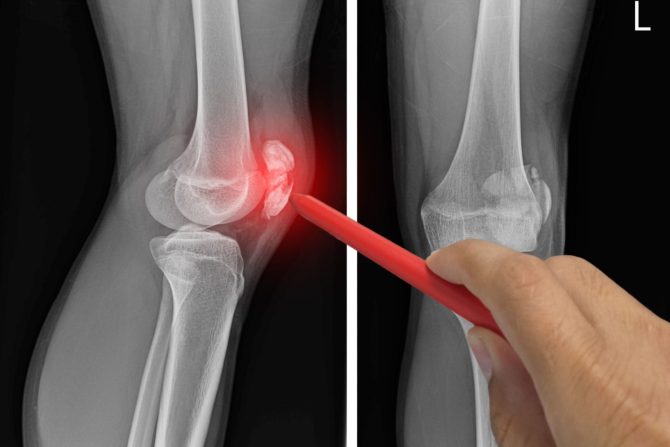

Povreda ili oštećenje meniskusa može da bude rezultat naglog uvrtanja ili rotacije kolena, naprezanje tokom čučnja, savijanja ili podizanja teških predmeta ili jakog udarca usled borbe ili druge sportske aktivnosti. Stepen povrede može da varira od naprezanja do delimičnog ili potpunog kidanja meniskusa. Lečenje simptoma povrede meniskusa varira u zavisnosti od stepena povrede i može da bude konzervativno kao što je odmor i "zaleđivanje" hladnim oblogama do drastičnijih intervencija kao što je operacija.

Meniskus je amortizer u obliku polumeseca u kolenu koji se nalazi između butne kosti (budrene kosti) i tibije (golenice). Svako koleno ima dva meniskusa. Jedan je na medijalnoj strani, bliži drugom kolenu, a drugi na bočnoj strani, najbliži spoljašnjoj strani noge. Tokom aktivnosti na stopalima, hrskavica meniskusa ublažava habanje okolne zglobne hrskavice, koja je zaštitni sloj na krajevima kostiju.

Pokidani meniskus je uobičajena povreda u kojoj je oštećena hrskavica koja čini jastuk meniskusa i narušen je integritet površine. Kao i kod većine povreda meniskusa, meniskus se može pokidati tokom sportskih aktivnosti poput trčanja i brzog okretanja. Kod starijih osoba, degeneracija hrskavice u kolenu, poznata i kao osteoartritis, može da oslabi meniskus tako da se pokida, čak i ako je malo sportske aktivnosti ili naprezanja. Poput pukotine u ledu, pukotina meniskusa u kolenu može da se širi u mnogo različitih pravaca.

Svaka aktivnost, koja uzrokuje nasilno uvijanje ili rotiranje kolena, posebno kada se punom težinom oslanjamo na njega, može da dovede do pucanja meniskusa. Ta povreda izaziva bol, otok i ukočenost. Takođe, čovek može da oseti blokadu pokretljivosti kolena i teško da može da ispruži  koleno. Konzervativni tretman, kao što su mirovanje, led i lekovi, ponekad je dovoljan da ublaži bol pokidanog meniskusa i da povreda vremenom zaceli sama od sebe. U drugim slučajevima, međutim, povreda meniskusa zahteva operaciju. Ako se sumnja na povredu meniskusa, ortoped može da traži rendgenske snimke i magnetnu rezonancu kako bi potvrdio dijagnozu i dodatno procenio stanje zgloba kolena.